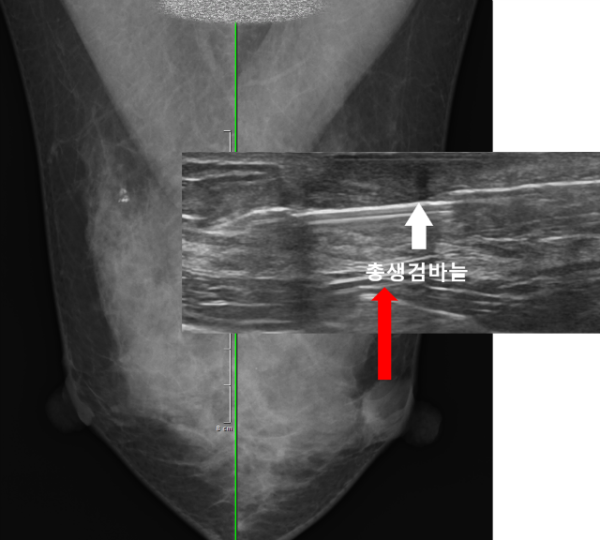

보다 정확한 진단을 하기위해 조직검사를 권유하였고 환자분도 이에 동의하셔서 이어서 총생검검사까지 진행하기로 하였습니다.

간단한 국소마취후 안전하게 조직검사를 시행하였으며 암이 의심되는 상황은 아니었기 때문에 응급으로 조직검사를 의뢰하진 않았습니다.